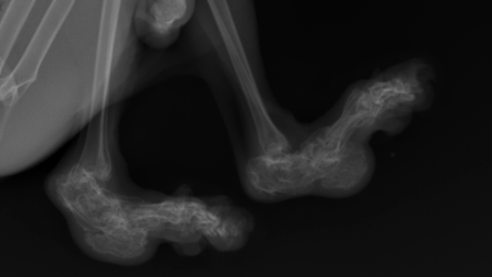

Хромающая кошка – это не просто неудобство, а серьезный повод для беспокойства. Порой, даже незначительное изменение в походке может свидетельствовать о серьезных проблемах со здоровьем, требующих срочного вмешательства опытного специалиста.

Скрытность симптомов. Кошки – животные, склонные скрывать боль. Они могут терпеть дискомфорт, пока он не станет практически невыносимым, что может привести к запущенным случаям, требующим более сложного и длительного лечения...